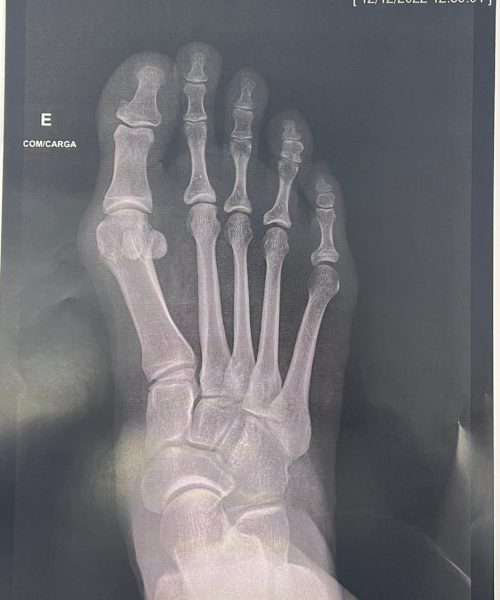

O que é a Cirurgia de Joanete Percutânea

A cirurgia de joanete percutânea é uma técnica que trata joanetes por meio de pequenas incisões e instrumentos especializados, buscando corrigir a deformidade do dedo do pé.

Essa cirurgia é indicada para pacientes com joanetes que buscam uma abordagem menos invasiva. É especialmente adequada para casos leves a moderados de deformidade no dedo grande.